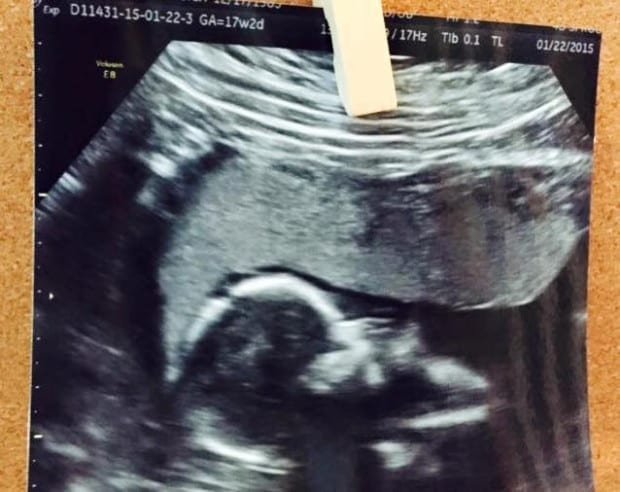

For the first few months, I took so many pregnancy tests. I was in denial. I could not believe it. Was this really happening? What if something happens? So many things ran through my mind, especially since the doctor saw two sacs and thought we might possibly have twins. That was an option for a few weeks. We had to wait 3 weeks until my next appointment and ultrasound to confirm things. We were only expecting one and the baby looked healthy.

I’m now 20 weeks and I just passed the “sick everyday, all day” stage. I feel good, I still don’t have much energy but I’m getting there. I’ve since found out that we are having a girl, a healthy beautiful little girl with the most adorable button nose.

She also loves to suck her thumb and do back flips during ultrasounds.